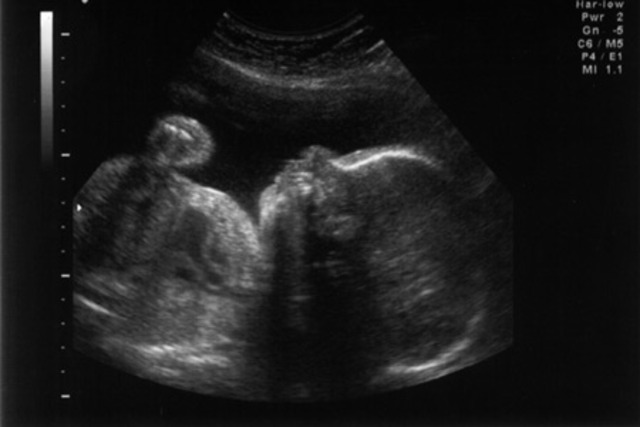

My mother is two months away from her due date, I am developing at normal rate and thus far there have been no complications.

My mother had noticed that I was not kicking and moving around which was unusual; after feeling me "summersault" in the womb. She goes to the doctor to find out what is wrong. They find that the imbilical cord was wrapped around my neck. They do an emergency C-section and I am born one month premature at 5 pounds 8 ounces.